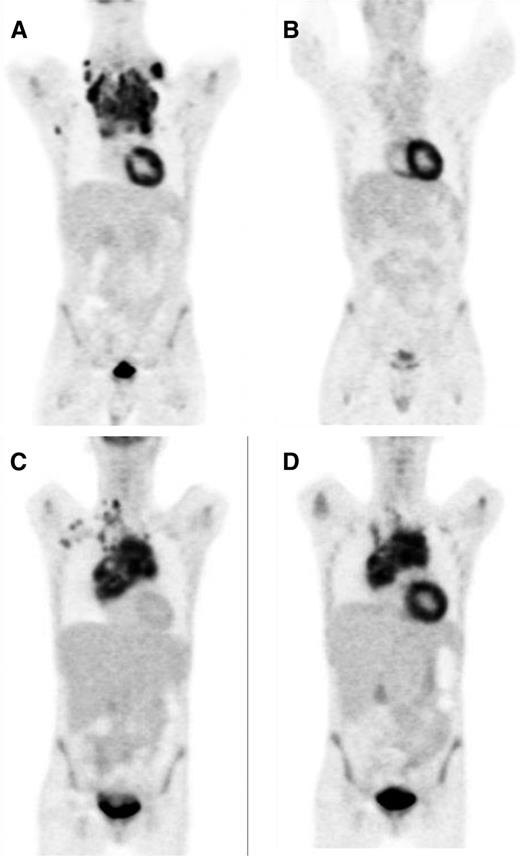

FDG-PET interim scans demonstrating negative and positive results. (A, C) Presentation scans showing uptake by HL. (B) Negative interim PET scan showing only physiological FDG uptake. (D) Positive interim PET scan showing residual uptake in the mediastinum.